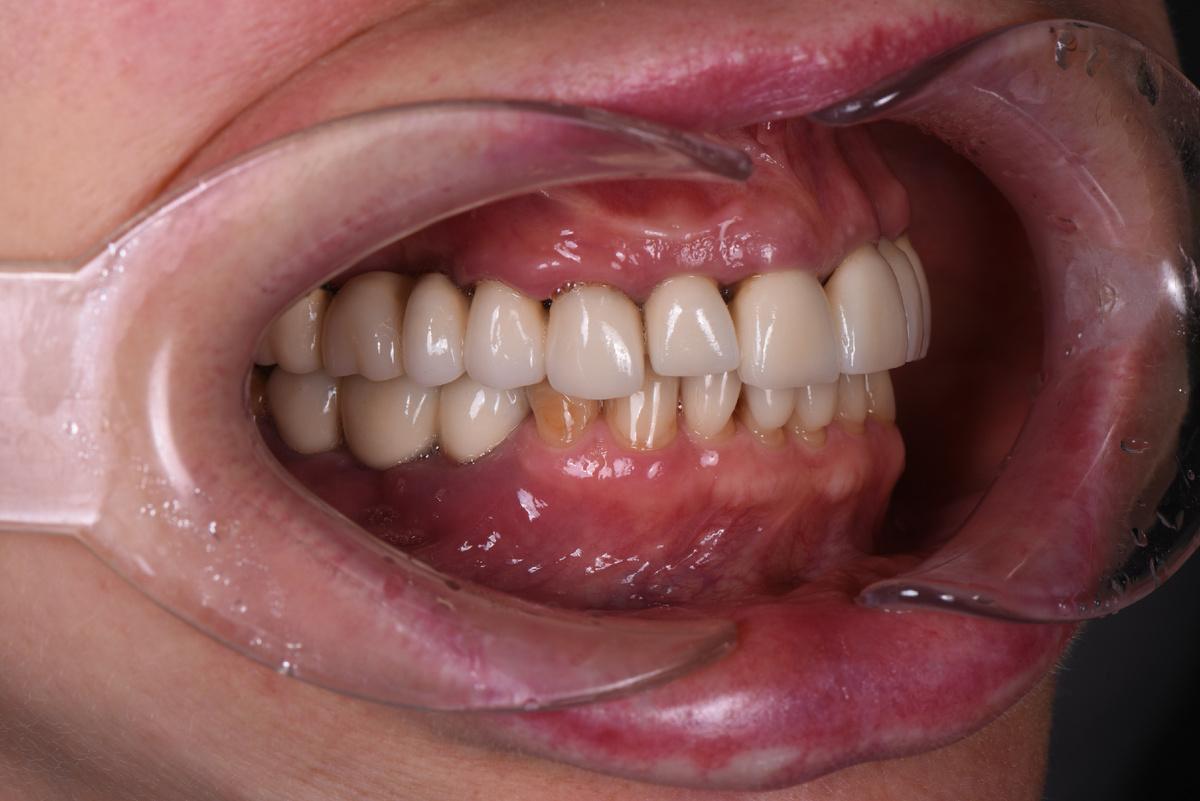

Результат спустя 1 месяц — на трёх фото ниже

Обратите внимание на то, что осталось от нижней челюсти слева. Сказать, что кости не осталось совсем — ничего не сказать